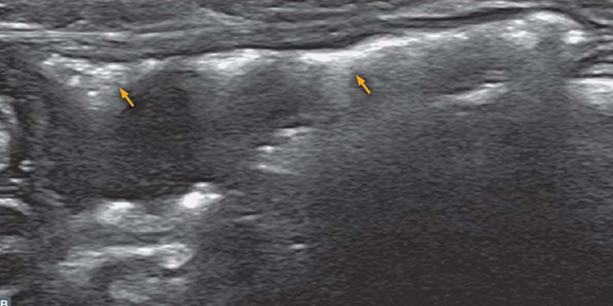

| Ultrasonography (Abd) | _Prostatitis |

![]() | - ์ ๋ฆฝ์ ์ ๋น๋์ mildํ hyperechogenecity๋ถํฐ, - ์ฌ๊ฐํ ๋น๋์ mottled hyperechoic~hypoechoic pattern (์ผ๋ฃฉ๋๋ฃฉํ ํจํด) ๊น์ง ๋ค์ํจ. - mottled sign โ ๊ฐ์ผ, ์ข ์ ์์ ๋ |